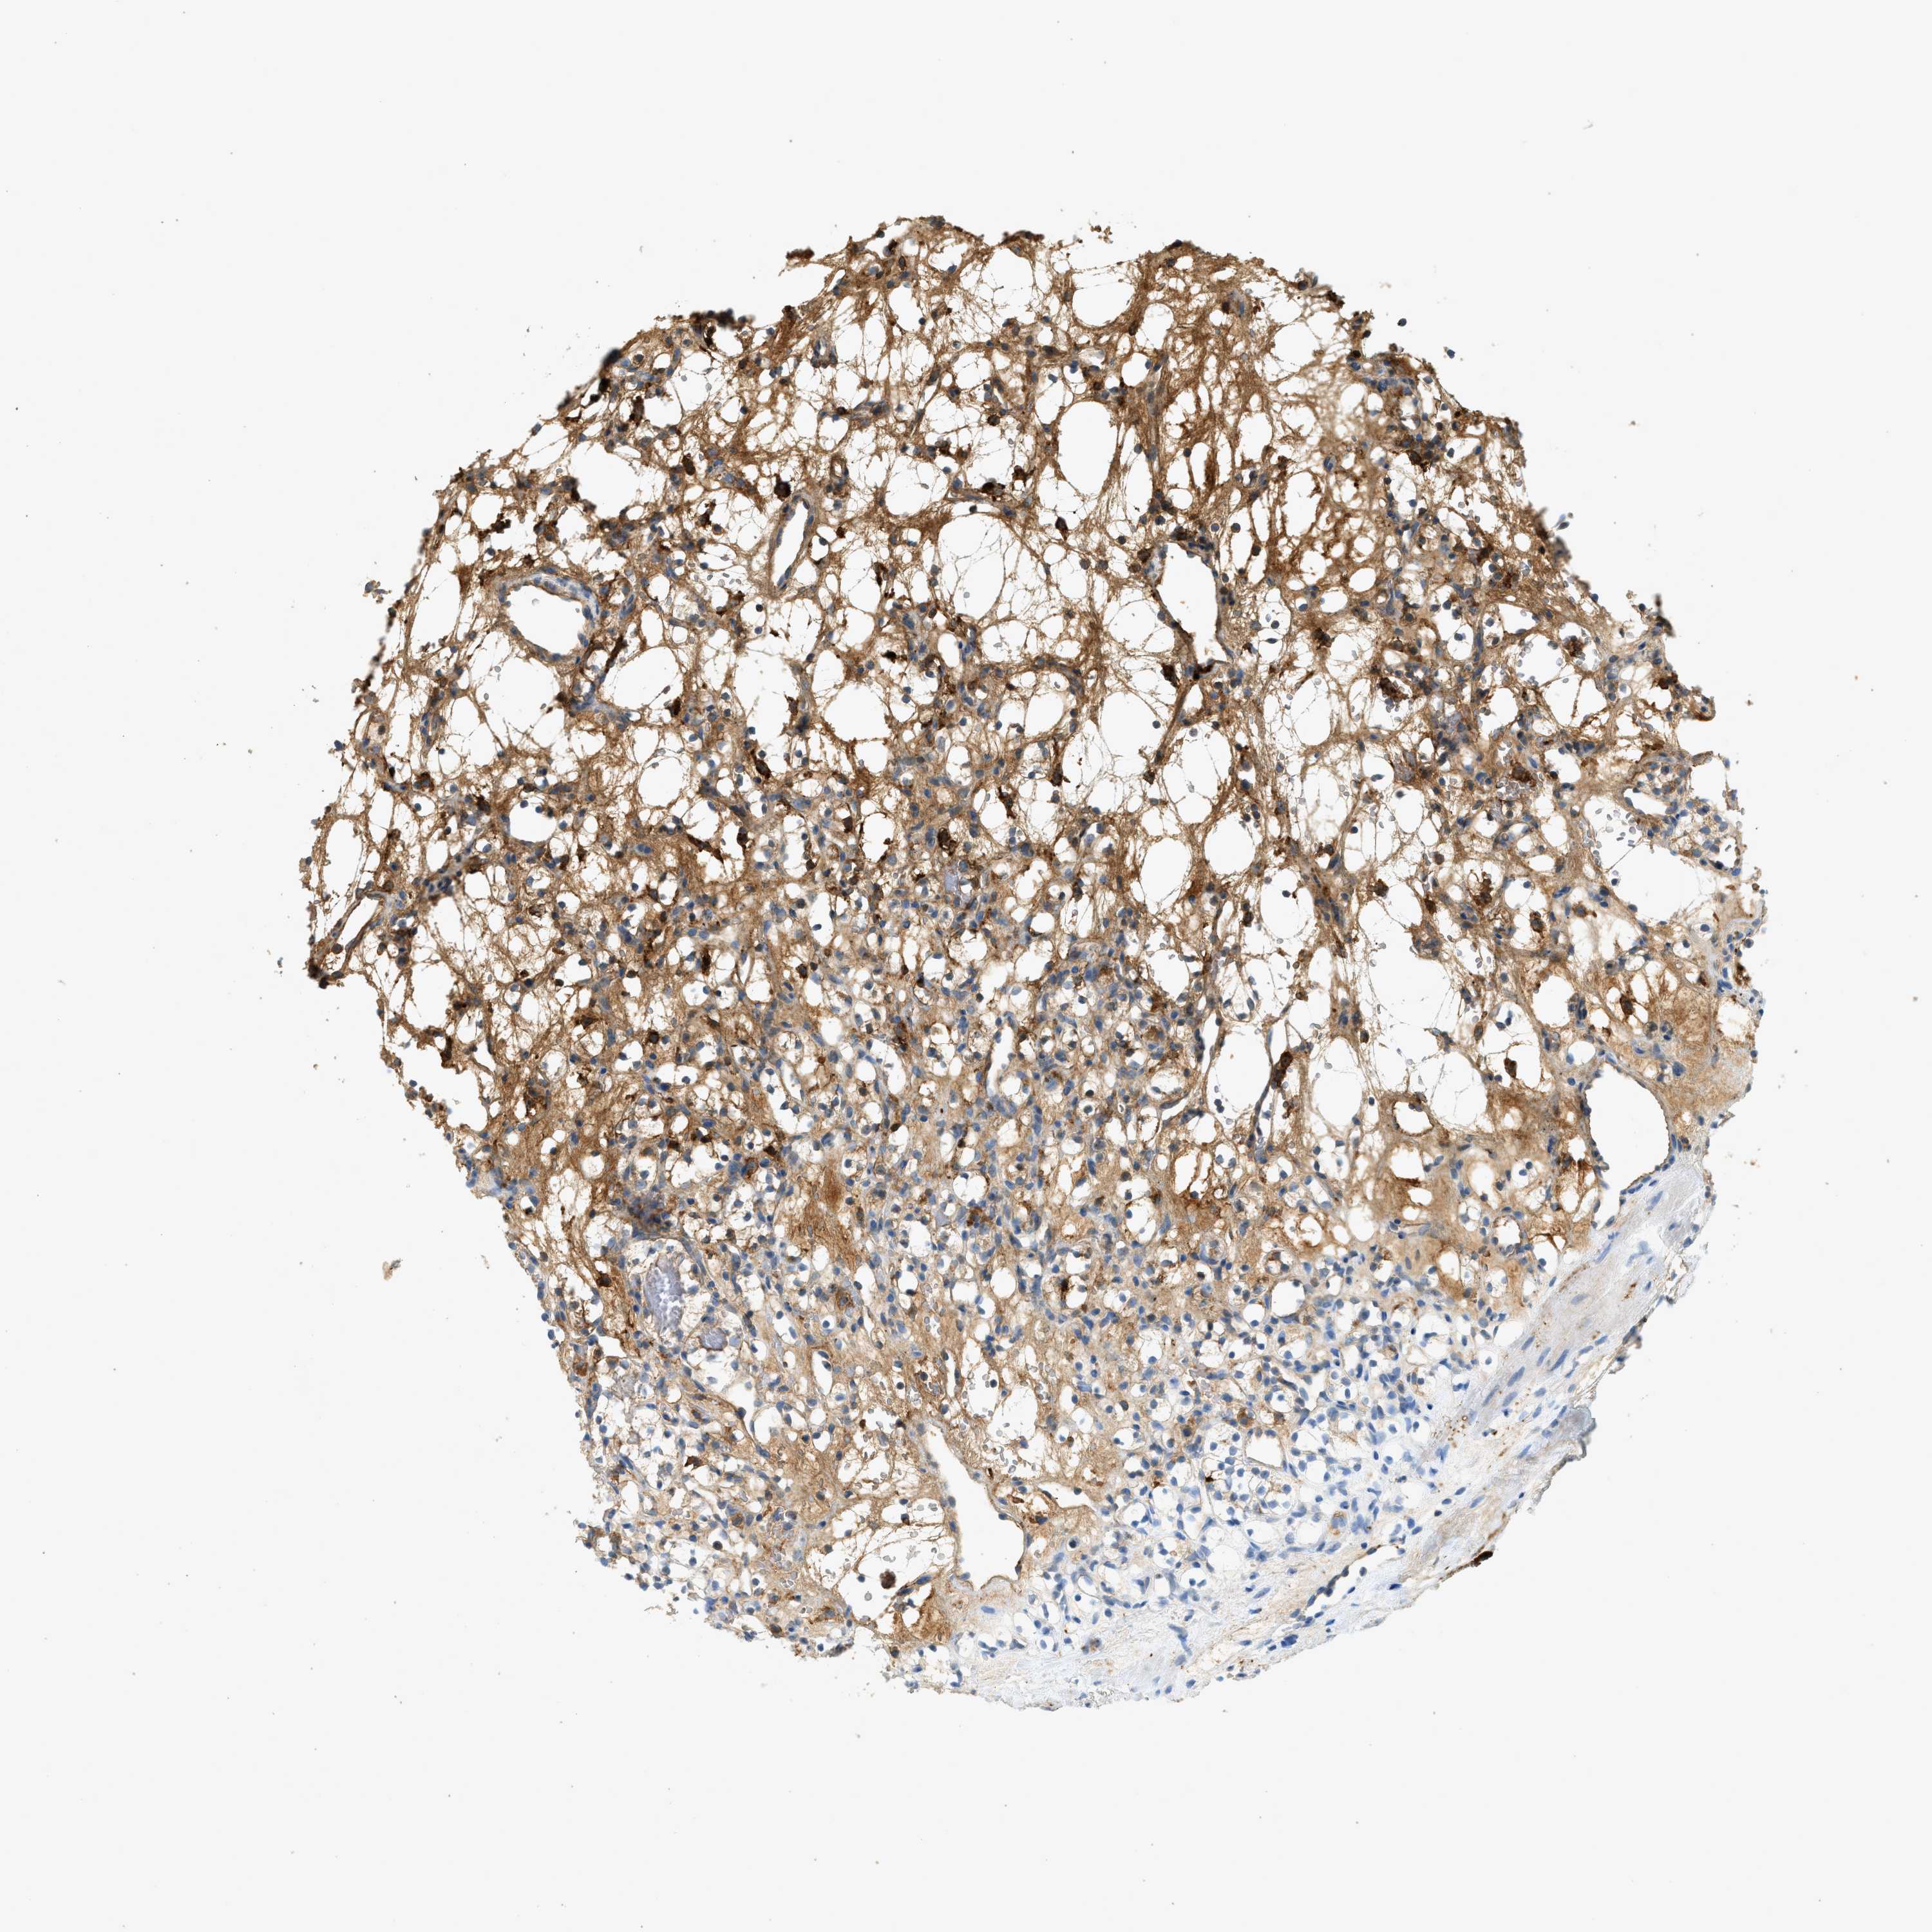

KIDNEY RENAL CLEAR CELL CARCINOMA (VALIDATION) - Interactive survival scatter ploti

The Survival Scatter plot shows the clinical status (i.e. dead or alive) for all individuals in the patient cohort, based on the same data that underlies the corresponding Kaplan-Meier plots. Patients that are alive at last time for follow-up are shown in blue and patients who have died during the study are shown in red.

The x-axis shows the expression levels (FPKM) of the investigated gene in the tumor tissue at the time of diagnosis. The y-axis shows the follow-up time after diagnosis (years). Both axes are complimented with kernel density curves demonstrating the data density over the axes. The top density plot shows the expression levels (FPKM) distribution among dead (red) and alive patients (blue). The right density plot shows the data density of the survived years of dead patients with high and low expression levels respectively, stratified using the cutoff indicated by the vertical dashed line through the Survival Scatter plot. This cutoff is automatically defined based on the FPKM cutoff that minimizes the p-score. The cutoff can be changed by dragging the vertical line or by entering a cutoff value in the square labeled "Current cut-off".

Under the Survival Scatter plot the p-score landscape (black curve; left axis) is shown together with dead median separation (red curve; right axis). Dead median separation is the difference in median mRNA expression between patients who have died with high and low expression, respectively. It is calculated as follows: median FPKM expression of dead patients with high expression - median FPKM expression of dead patients with low expression. This is intended to aid the user in visually exploring custom cutoffs and the associated p-scores and dead median separation.

Individual patient data is displayed and can be filtered by clicking on one or more of the category buttons on the top of the page. Categories describing expression level and patient information include: high, low, alive, dead, female, male and tumor stages. The scale of the x-axis can be toggled between linear and log-scale by clicking on the "x log" button. Mouse-over function shows TCGA ID, patient information and mRNA expression (FPKM) for each patient.

& Survival analysisi

Kaplan-Meier plots summarize results from analysis of correlation between mRNA expression level and patient survival. Patients were divided based on level of expression into one of the two groups "low" (under cut off) or "high" (over cut off). X-axis shows time for survival (years) and y-axis shows the probability of survival, where 1.0 corresponds to 100 percent.

F2 is validated prognostic, high expression is unfavorable in Kidney Renal Clear Cell Carcinoma (validation)

Best expression cut offi

: 0.22

TCGA RNA samplesi

RNA-seq data is reported as average FPKM (number Fragments Per Kilobase of exon per Million reads), generated by the The Cancer Genome Atlas (TCGA) .

Normal distribution across the dataset is visualized with box plots, shown as median and 25th and 75th percentiles. Points are displayed as outliers if they are above or below 1.5 times the interquartile range. FPKM values of the individual samples are presented next to the box plot.

Average pTPM 4.4

Number of samples 100